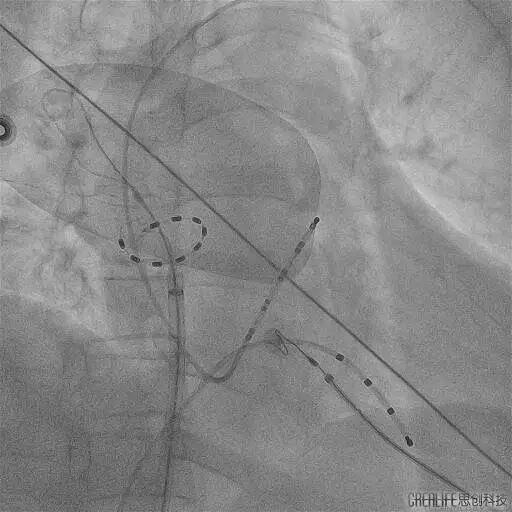

今年60岁的崔伯伯(化名)和59岁的张阿姨(化名)因房颤发作频繁,极大的影响日常生活,甚至呈焦虑状态,遂就诊武汉亚洲心脏病医院;在完善心脏彩超、食道超声及左房CT等一系列检查后,张劲林主任和韩宏伟主任经过充分的评估和与患者及家属的知情确认后,选择脉冲电场消融术为其治疗,该项技术以其高安全性、高效性和微创性,为房颤患者带来了更为优质的治疗选择。术中使用脉冲电场消融导管分别在四根肺静脉进行消融,每根肺静脉口内定位4个位置,前庭定位6-8个位置,逐次放电(电压1500V) 。每根肺静脉首次放电,肺静脉电位振幅即可明显下降至消失,四根肺静脉均完成肺静脉电隔离。

PS导管通过外鞘送入左心房,在二维引导下到达目标肺静脉,在导丝指引下调整导管成环进入肺静脉,使环形电极贴靠肺静脉口/前庭。

观察电极形变并明确电位,确认贴靠良好后依次对每个每支静脉进行口部4次+前庭6-8次的脉冲消融,对上腔静脉补充4次消融,完成四根肺静脉(PVI)和上腔静脉的环形隔离。

PS导管行LSPV消融

PS导管行LIPV消融